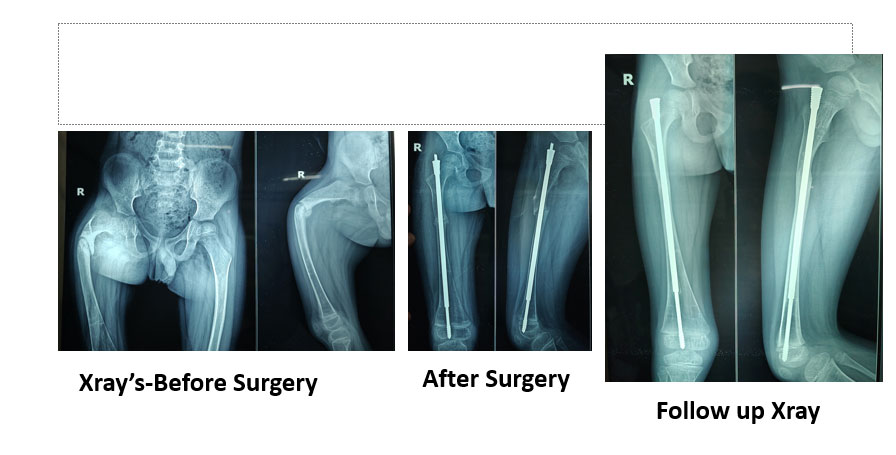

Osteogenesis Imperfecta

View Details